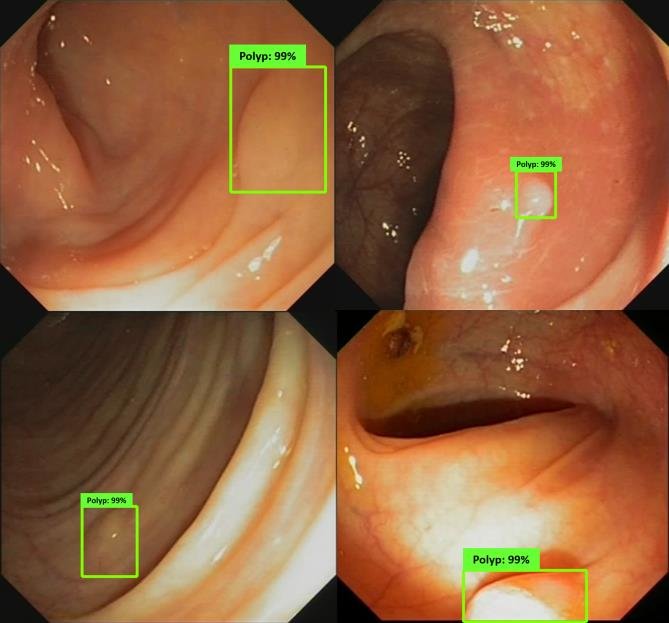

Colonoscopy Polyp Detection

Advanced medical image processing for enhanced diagnostic accuracy.